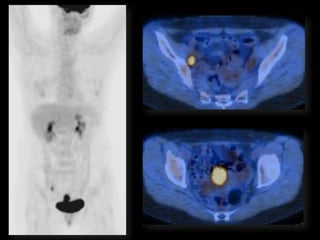

HISTORY

โ€ข   42 yo female

โ€ข   Recent immigrant from China

โ€ข   C/O postcoital and intermenstrual bleeding

โ€ข   Abnormal GYN exam

โ€ข   Abnormal biopsy

โ€ข   Further imaging performed

MRI findings - Stage IIB

with PET/CT - Stage IIIB

Role of MR Imaging in Tx Stratification

of GYN (Cervical) Cancer

โ€ข Cervical Cancer โ€“ 2nd most common ca in women

worldwide

โ€“ Developing countries; pk 30-40 yrs

โ€ข FIGO classification โ€“ revised in 2009 from just clinical to

incorporate cross-sectional imaging (CT, MR)

โ€ข Staging accuracy of MR 85-96%

โ€“ Best test to assess tumor size and location; invasion into

parametria, pelvic side wall, adjacent organs; local nodal enlgment

โ€ข PET/CT helpful in staging advanced disease

โ€“ Demonstrates unexpected sites beyond pelvis

โ€ข Treatment options

โ€“ Radical surgery - early stage (IA, IB1, IIA1)

โ€“ Primary Chemo and Radiation โ€“ bulky IB2 or IIA2, or local

advanced (IIB or greater)

Sala et al. Radiology 2013; 266: 717.